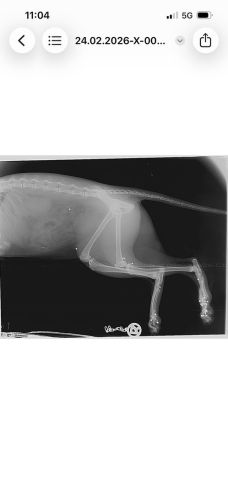

Nach diesem Zwischenfall waren alle vier Katzen verschwunden. Die Betreuerinnen suchten jeden Tag und stellten schließlich eine Kamera auf. Es wurde auch nochmals Kontakt mit dem Jäger aufgenommen – die Ungewissheit war unerträglich, man bat ihn um Ehrlichkeit, in der Hoffnung, Gewissheit zu bekommen und die Suche einstellen zu können. Doch der Jäger stritt weiterhin ab, auf die Katzen geschossen zu haben. Die Suche nach den Katzen ging also weiter, bis schließlich eines Tages eine der verschollenen Katzen auf den Kamera-Aufnahmen zu sehen war, zwei Wochen später tauchte eine zweite Katze auf den Aufnahmen auf. Nach insgesamt sechs Wochen Suche konnten zwei der Katzen endlich gesichert werden. Doch beim Tierarzt der nächste Schock: eine der Katzen war von mehreren Schrotkugeln getroffen worden und musste starke Schmerzen haben.

Nach Auswertung der Röntgenbilder liegt der Schluss nahe, dass die Katze von unten beschossen worden sein muss – die Betreuerinnen erzählen, dass die Katzen immer gerne auf den Balken im Stadl geschlafen haben. Es ist also ziemlich klar, was da passiert sein muss – und es stellt sich die Frage, wie abgebrüht man sein muss, um zu so etwas fähig zu sein. Bei einer Katze wurden die Kugeln, die unmittelbar unter der Haut lagen, mittlerweile entfernt – die tieferliegenden Kugeln sollen erst dann entfernt werden, wenn sie der Katze Probleme bereiten. Man will die Katze im Moment nicht noch mehr stressen. Der Kater, der ebenfalls gesichert werden konnte, ist bis heute so stark traumatisiert, dass eine Untersuchung bisher noch gar nicht durchgeführt werden konnte. Zumindest waren bei ihm aber keine Kugeln unter der Haut zu ertasten. Von den beiden anderen Katzen, die an der besagten Futterstelle versorgt worden waren, fehlt bis heute jede Spur. Es ist leider davon auszugehen, dass sie es nicht geschafft haben.

Hier noch weitere Röntgenbilder der angeschossenen Katze und das Schreiben der Staatsanwaltschaft Augsburg: